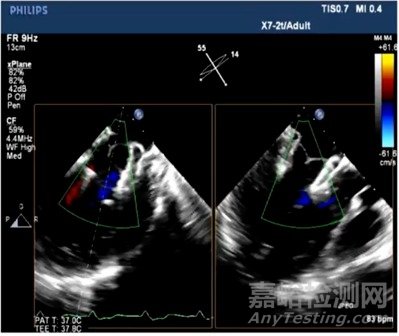

目前,Mi-thos®已成功于復(fù)旦大學(xué)附屬中山醫(yī)院、西京醫(yī)院完成多例探索性臨床人體應(yīng)用(Implement),應(yīng)用結(jié)果顯示,所有患者手術(shù)流程順利,術(shù)后瓣膜功能明顯好轉(zhuǎn),無嚴(yán)重并發(fā)癥發(fā)生,瓣膜反流消失,隨訪期臨床效果令人滿意,充分體現(xiàn)了Mi-thos®的安全性與有效性。

瓣膜釋放后,TEE顯示反流消失